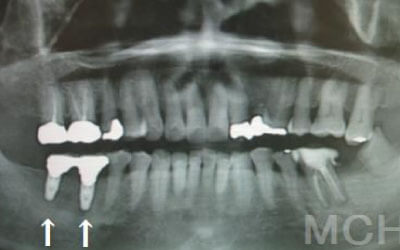

2 神経を傷つけるリスク

インプラント治療では、顎の骨内を通る神経を傷つけるリスクがあります。

ただし、事前にCTで三次元的に神経との距離を測り、治療計画を慎重に立てれば、心配することはありません。

また、当院では過剰に削らないようにするためのストッパーも使用しています。